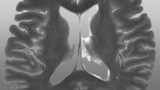

よくわかる脳MRI

画像診断に関わる人であれば必須の本です。

脳外科、神経内科以外でも放射線科に興味がある人もおすすめです。

実際、私も研修医の時に放射線科の上級医からオススメされて購入しました。

正常解剖から脳腫瘍、脳血管障害、変性疾患など多岐にわたります。

こちらも見開き1ページで多くのページが完結しているところが読みやすいです。

基本構造としては、左ページに画像所見、右ページが解説ページとなっています。